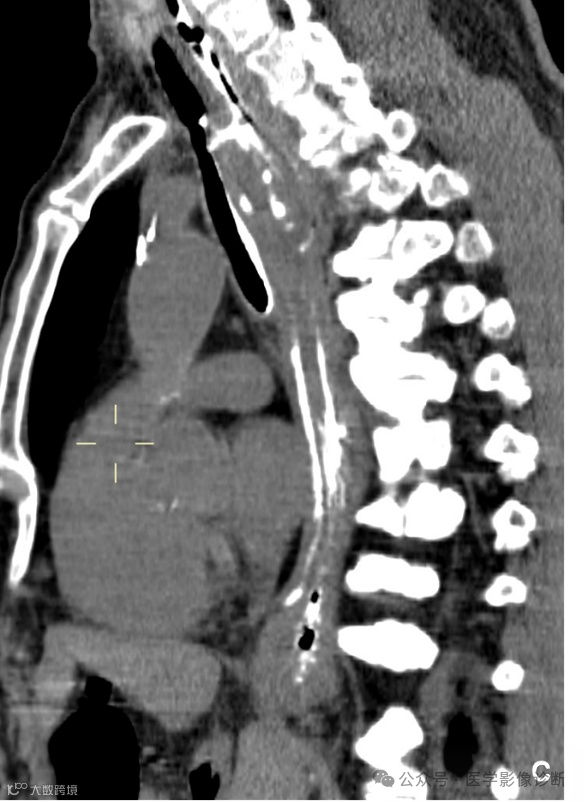

患者,男性,67岁,食管癌术后。

轴位 CT 显示食管癌术后变化(a, b)。然而,由于临床提供的申请表没有提醒,放射科医生只描述了术后变化,没有提及气管食管瘘。多平面成像(MPR)可以更好地显示瘘管。根据口服造影剂的使用情况,放射科医生应该明白医生想要观察是否发生了瘘管。